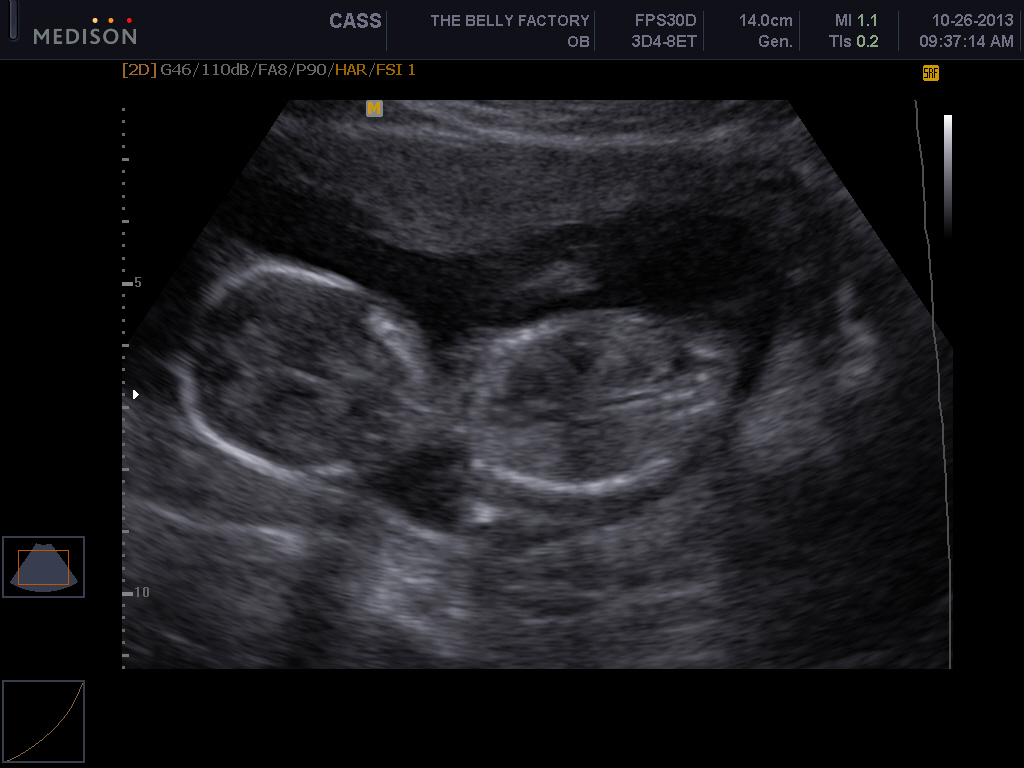

2nd Trimester

Re: It's a.....